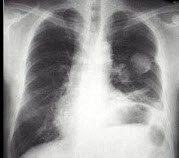

6、单项选择题

男,5岁,临床考虑先心病室间隔缺损,结合图像,下列描述正确的是()

A.肺淤血

B.正常肺

C.肺泡性肺水肿

D.间质性肺水肿

E.肺充血